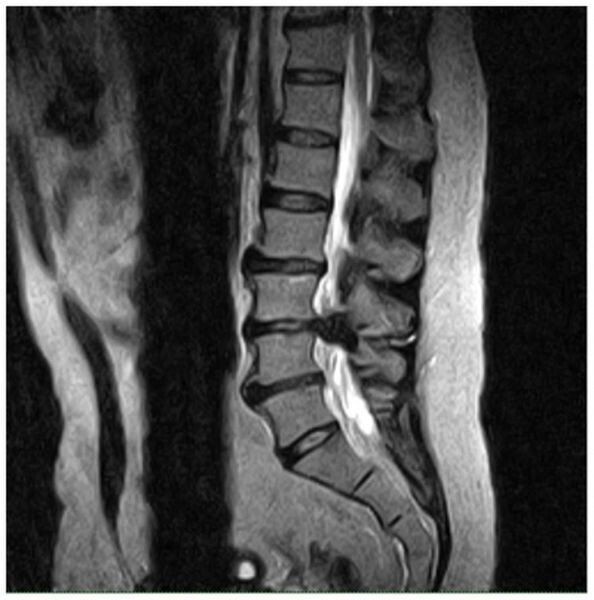

МРТ спины: 3 «страшные» находки, которые часто НЕ нужно лечить

Вы сделали МРТ спины из-за боли и теперь в ужасе: в заключении написали «грыжа», «протрузия», «артроз». Мир рухнул? Вовсе нет. Доказательная медицина говорит нам важную вещь: часто нет прямой связи между тем, что видно на МРТ, и вашей болью.

Крупные исследования (например, знаменитая работа Brinjikji et al., 2015) показывают: у огромного количества здоровых людей без всякой боли в спине на МРТ находят «ужасные» изменения.